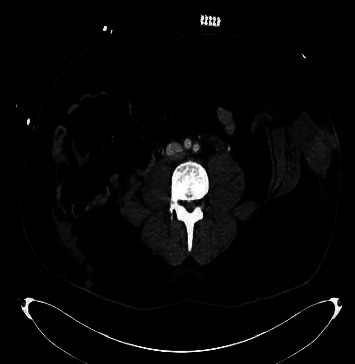

Figure 2.

Abdominal CT. Bilateral herniation of abdominal viscera.